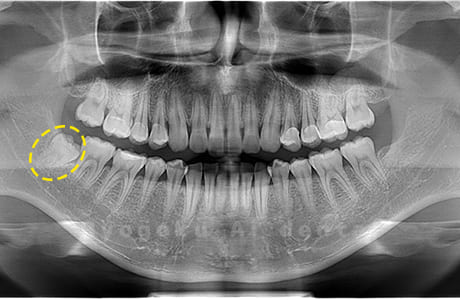

Case01

- 原因

- 水平埋伏智歯

- 治療内容

- 下顎の水平埋伏智歯を抜歯

<リスク・副作用>

手術後は痛み、腫れ、痺れなどの副作用が生じる場合があります。